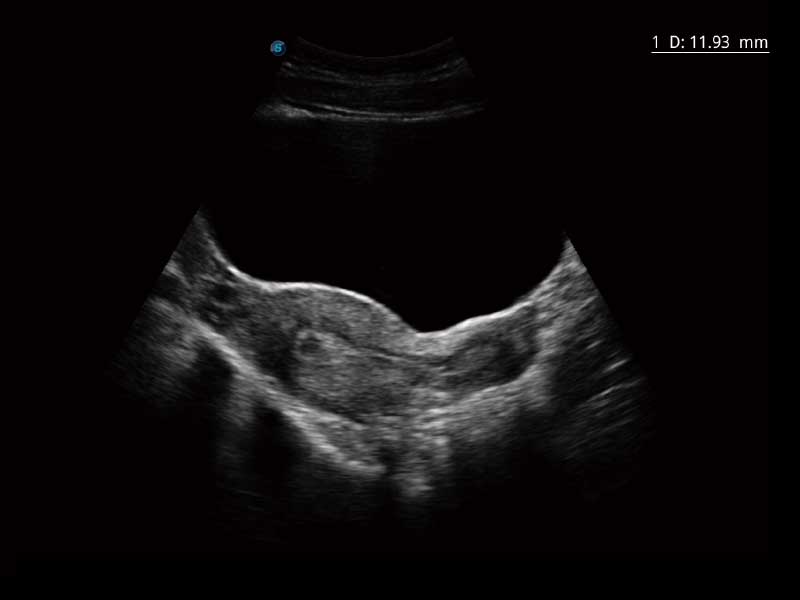

μ-Scan微米成像、空间复合成像、高分辨率血流成像。